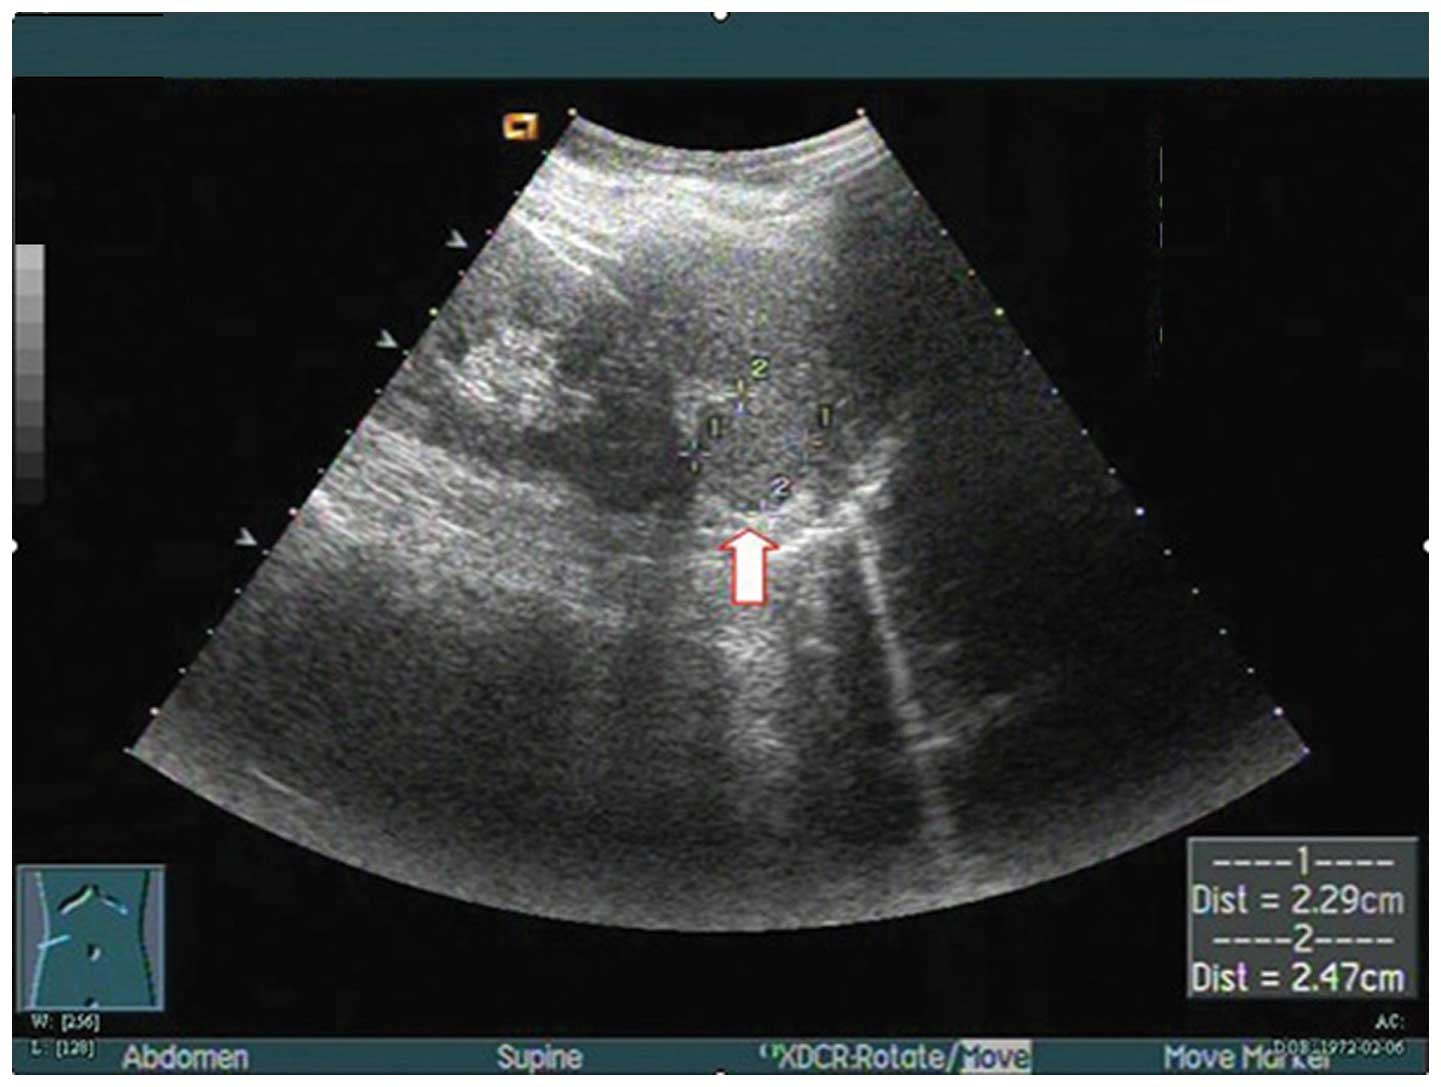

Rare presentation of a right retroperitoneal accessory spleen: A case report

An accessory spleen is a congenital malformation, which is defined as ectopic splenic parenchyma. Here, an extremely rare case of a right retroperitoneal accessory spleen, mimicking a retroperitoneal neoplasm, is reported. A 40-year-old woman was referred following the incidental detection of a retroperitoneal neoplasm. Computed tomography and magnetic resonance imaging scans confirmed the presence of a retroperitoneal neoplasm at the hepatorenal recess. Retroperitoneoscopic excision was conducted, with excellent results. Pathological examination of the resected specimen revealed splenic tissue. In conjunction with a review of the literature and a discussion of the salient radiological features, the present case highlights the requirement for accurate preoperative diagnosis of an accessory spleen in the right retroperitoneal space, in order to avoid unnecessary surgical intervention.